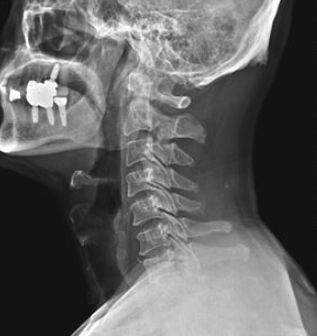

환자분이 가져오신 CT와 제가 새로 찍은 X-ray를 보니

역시나 경추 3-4번, 6-7번 추간판탈출증이 있더라고요.

그림9.png 촬영 일시: 2025.02.11

<Fig 1. 경추 X-RAY 영상>